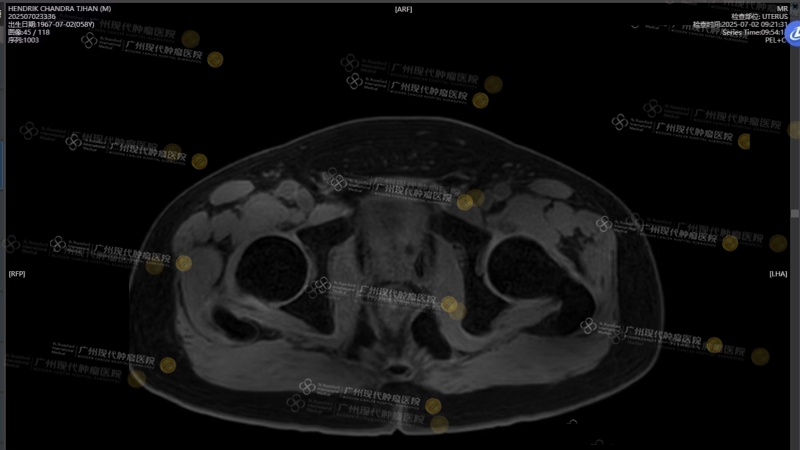

Khi trở về Indonesia, ông tái khám định kỳ, và mỗi lần chỉ số PSA giảm đều tiếp thêm niềm tin cho ông. Kết quả MRI mới nhất cho thấy khối u đã thu nhỏ rõ rệt, gần như biến mất.

Sau điều trị xâm lấn tối thiểu, khối u tuyến tiền liệt khoảng 3 cm gần như “biến mất hoàn toàn”.